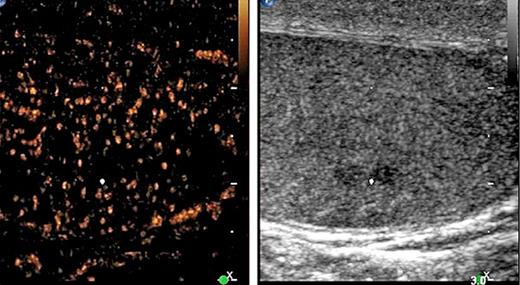

5th patient: this 23-year-old man underwent orchiectomy for marker-negative testicular seminoma at another institution. CT revealed intrathoracic nodules suspicious for mediastinal lymph node metastases. Accordingly, 4 cycles of BEP chemotherapy were administered. Restaging revealed unchanged mediastinal lymphadenopathy (Fig. 4). Then, the patient was referred to our institution for further management. Thorough pulmonological examination including transbronchial biopsy disclosed sarcoidosis-like lymphadenopathy, and thus metastatic disease was excluded. In view of these results, it must retrospectively be assumed that this patient had sarcoidosis synchronously with seminoma rather than having metastatic disease. Accordingly, the serum miR371a-3p level was RQ = 0.0 at the time of re-staging after chemotherapy. Unfortunately, no miR-levels were measured at the time of first presentation. Although speculative, one would assume that miR371a-3p levels had probably been low after orchiectomy for seminoma because the mediastinal lymphadenopathy had not changed ever since. By retrospective consideration, the normal marker level would have indicated the absence of metastases at the outset and accordingly, the patient could have been spared unwarranted chemotherapy and excessive diagnostic procedures apart from emotional distress from extended treatment.